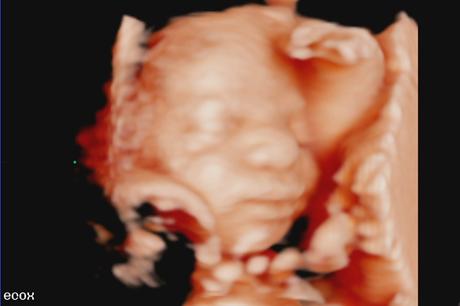

- Ecografía 3d: se ve el bebé sin movimiento

- Ecografía 4d: se ve el bebé en movimiento dentro del útero

- Ecografía 5d: se ve el bebé de manera más real, gracias a la luz y al tipo de máquina que realizan estas ecografías.

En una ecografía 4d conseguirás ver la carita de tu bebé, no pienses en una foto en primer plano, es complicado, porque los bebés están dobladitos, pero también puede conseguirse. Podrás ver como tu bebé bosteza, se coge los pies, abre y cierra las manos, agarra el cordón umbilical, duerme, saca la lengua… Hace siglos ver al bebé así hubiera sido “brujería” pero ahora es un capricho que todas las mamás podemos permitirnos, porque no es caro.